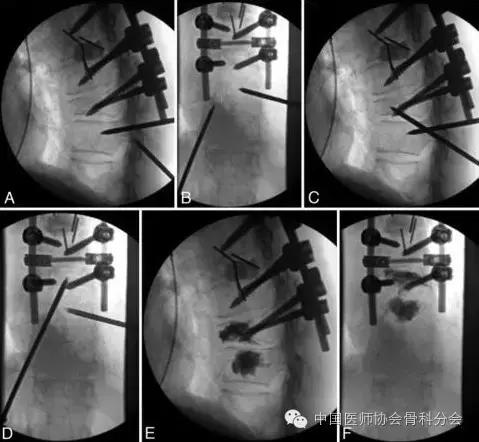

病例1:78岁女性,曾因胸7病理性骨折行后路椎体切除椎弓根钉置入胸5-9植骨融合内固定术,术后2个月出现了固定节段下部的骨折,导致后凸加重及皮肤隆起(内固定),但没有合并感染。胸10椎体行传统的经椎弓根椎体成形术,胸9由于椎弓根已经被椎弓根螺钉占据,所以选择胸10另外一侧椎弓根外缘外1cm处为进针点,经胸10椎弓根-胸9/10椎间盘,自椎弓根的下外后向头端、内侧、前方穿刺进入胸9椎体,并注入骨水泥来完成手术。患者术后症状缓解明显。考虑患者营养状况差,二期行部分内固定取出和清创术。

图3. 病例1.术中的正位X线片。A和B:胸10椎体穿刺完成。穿刺点在椎弓根的下后外侧。C和D:穿刺针进入胸9椎体中部。E和F:骨水泥注入以后有少量进入胸9/10椎间隙